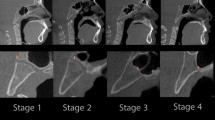

Zhang et al.4 found two ossification patterns of the postsphenoid cartilage. In the first pattern, the medial postsphenoid ossification centers fused at an early stage of development (CRL 120–140 mm, 17w0d–18w0d). Contrariwise, in the second pattern, the medial postsphenoid ossification centers remained separate for a longer period and fused at a later stage (CRL 170 mm, 21w0d). These authors also measured the distance between the two most distant points of the postsphenoid ossification center, which reached the mean values: 3.35 ± 0.58 mm in fetuses of CRL 120 mm (17w0d), 4.72 ± 0.48 mm in fetuses of CRL 130 mm (17w5d), 4.41 ± 0.65 mm in fetuses of CRL 140 mm (18w2d), and 4.47 ± 0.69 mm in fetuses of CRL 170 mm (20w6d). For a single postsphenoid ossification center the mean distance was 3.72 ± 0.58 mm, and for a double postsphenoid ossification center the mean distance reached the value of 4.83 ± 0.45 mm. In our study, all examined individuals referred to the gestational age range of 18–30 weeks, with an average transverse diameter of the postsphenoid ossification center ranging from 3.02 ± 0.08 to 4.50 ± 0.01 mm.